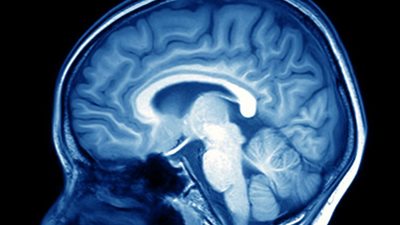

قالت أميمة أحمد، مدير أعمال الفنان إيمان البحر درويش، إن المطرب يمر بأزمة صحية بعد تعرضه لنزيف في المخ وخضوعه لجراحتين خطيرتين وظل فترة طويلة في العناية المركزة. واضافت في مداخلة هاتفية لبرنامج «كلام ...